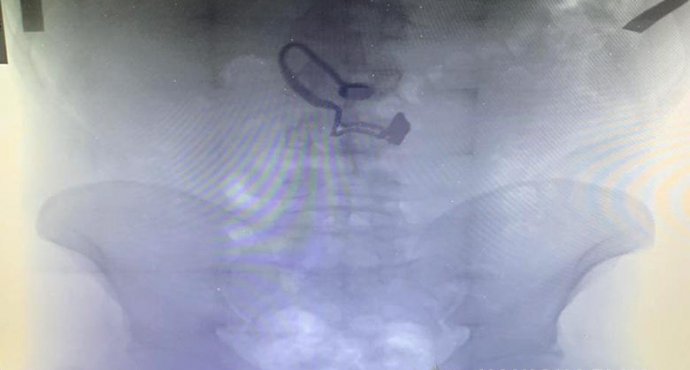

“Під час медогляду на рентген знімку затриманого лікарі виявили прикрасу”, – відзначили у поліції.